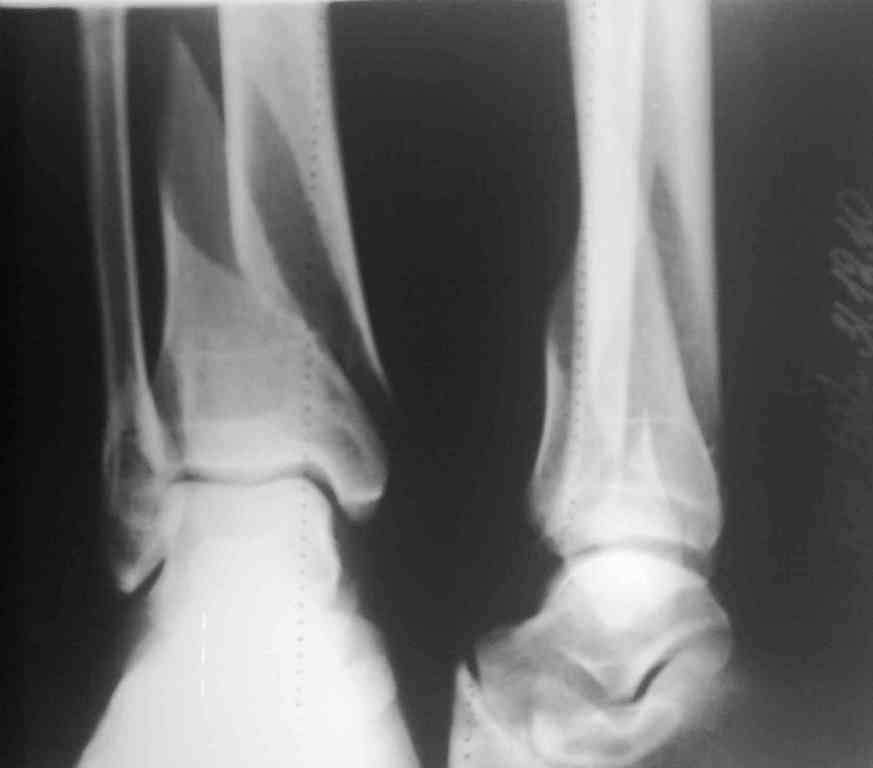

Необходим ли МОС обеих костей голени?

На сегодняшнем обсуждении данного клинического примера у нас возникла дискуссия о целесообразности металлоостеосинтеза латеральной лодыжки.

Предложений несколько:

1)стабильный МОС большеберцовой + гипсовая иммобилицация сегмента 3 - 4 нед;

2) стабильный МОС большеберцовой кости и дальнейшее ведение пациента без внешней иммобилизации;

3)стабильный МОС обеих костей голени.

Какие у Вас мнения по данному случаю?